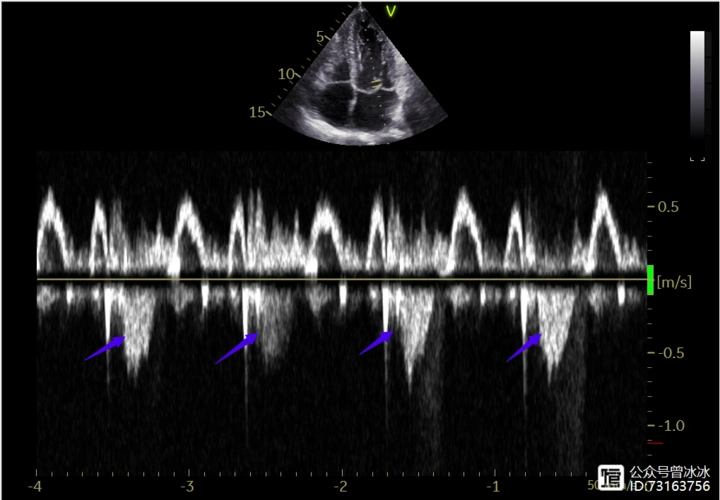

左室流出道的频谱二尖瓣反流频谱